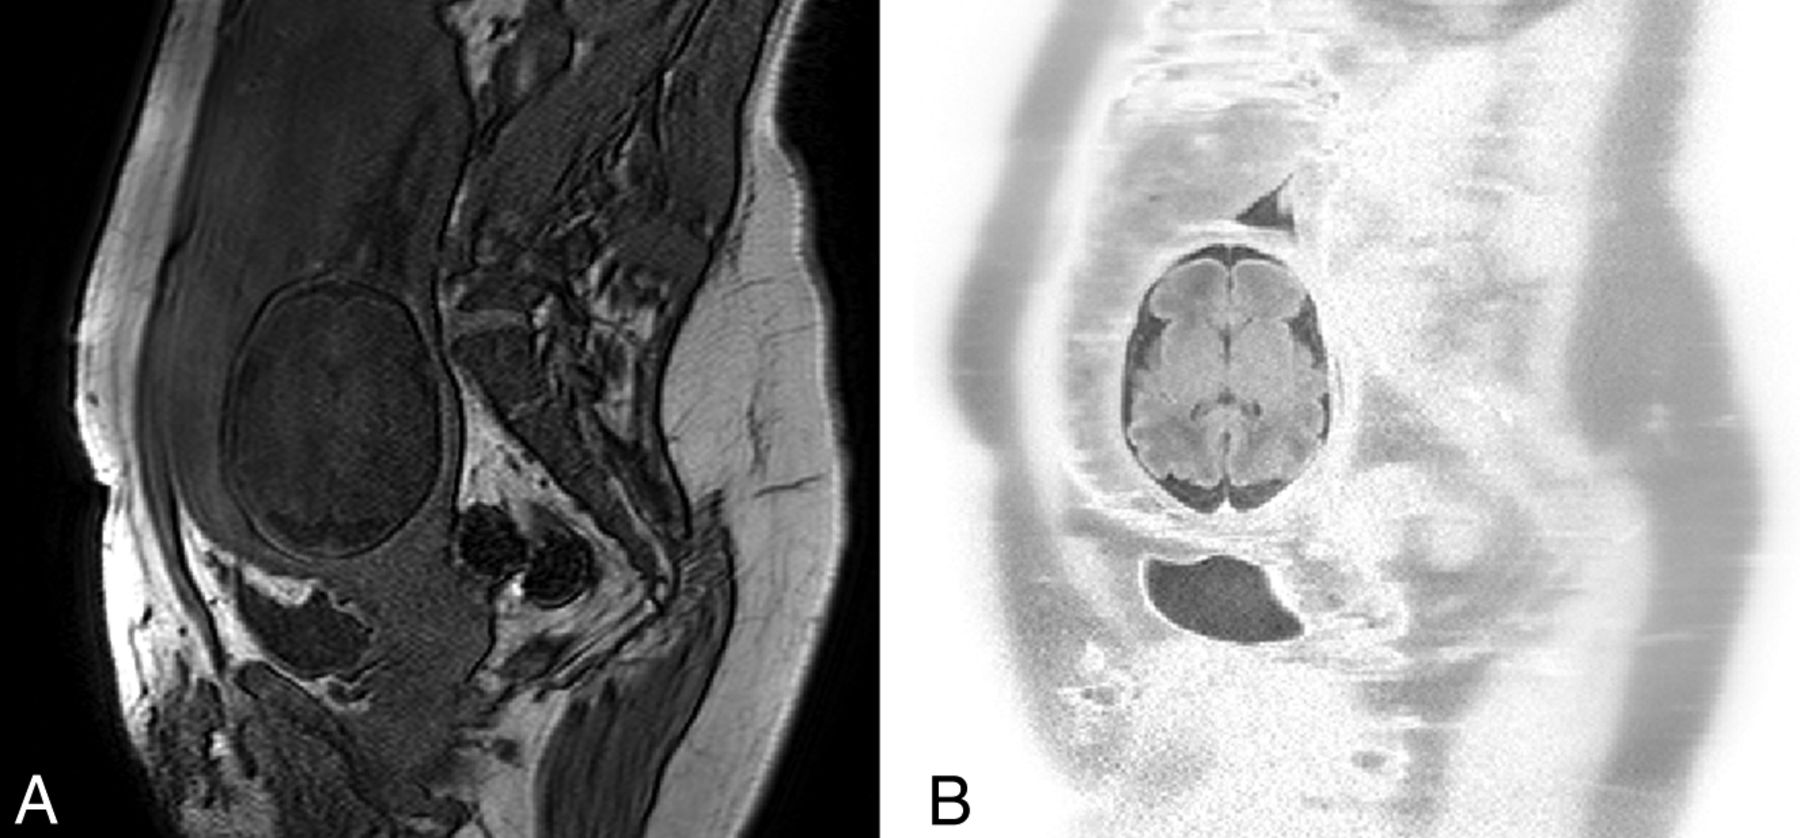

Motion artifacts may present as “blurring” (Fig 5C), “ghosting” (Fig 5J), contrast changes (Fig 5P), and even signal voids (Fig 5B) as described in the previous section. Blurring is similar to motion blur in photography, producing a marked decrease in spatial resolution; in the case of MR imaging though this is mostly evident in the phase-encoding direction, regardless of the actual direction of the original motion. Ghost images comprise lines concentric or parallel to bright imaged structures, such as subcutaneous fat on T1-weighted images, and represent full or partial replicas of the original static source. These should not be confused with the similarly appearing Gibbs ringing artifacts due to data truncation (Fig 6). Additionally, contrast changes and signal void may occur with very fast patient motion.

Successive axially planned sections of a single-shot fast-spin-echo acquisition at 1.5T (TR, 1000 ms; TE, 127 ms; section thickness, 4 mm; scanning duration, 26 seconds) of a 32-week-old fetus (E) with significant fetal motion occurring during data acquisition and resulting in blurring (C, J, M), contrast changes (P), and ultimately signal void when motion is extreme (B). Please note that though sections were planned in the axial plane, fetal movement resulted in plane transposition in the produced images (A–P) (fetal brain is circumscribed in red to distinguish it from neighboring maternal tissues).